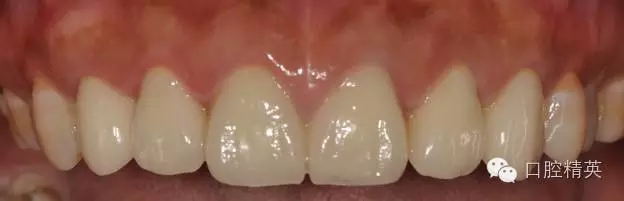

修復(fù)體完成后正面觀